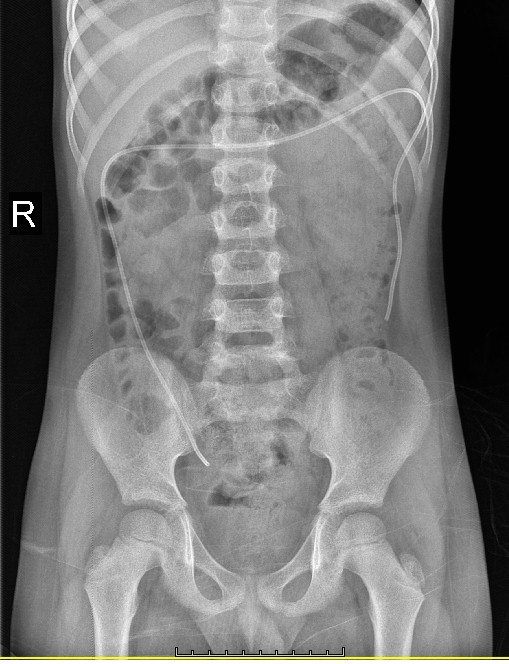

A CT scan of the head established a moderate degree of hydrocephalus by a satisfactorily situated right ventricular catheter (Figure 1). A shunt series presented a disconnection of the distal tube of the shunt (Figure 2). The distal part was free in the abdominal cavity, especially in the direction of the right inguinal canal. The shunt tube was not presented in the cervical x-ray. It appeared that the disconnection had occurred in the distal part of the shunt pump system in the neck. An abdominal and pelvic sonography did not show any evidence of mass or fluid collection or signs of infection. After urgent aspiration of the proximal valve the patient awoke quickly. Blood and CSF culture and analysis were negative for infections.

The patient experienced a shunt revision. The abdominal incision was revived, and the distal catheter was found and removed gently from the abdominal cavity (Figures 3 & 4). The original shunt system consisted of a Medtronic Delta Neonate Valve that was substituted by a completely new Medtronic Delta Unitised Shunt due to the patient’s age. Then, in a sterile fashion, the surgery was finished.